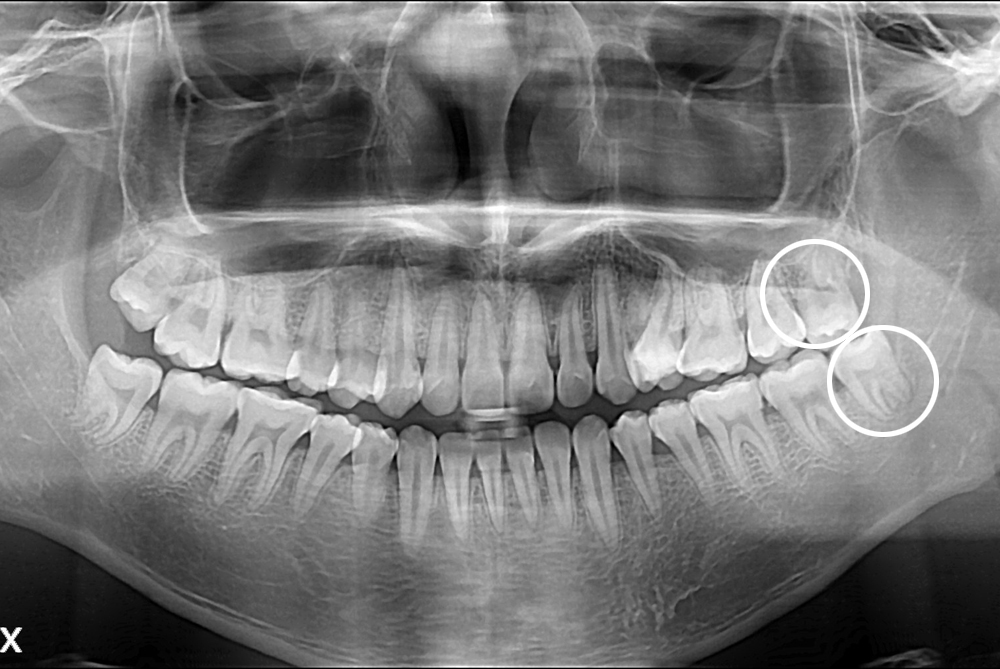

정상교(후).jpg

치료후 : 2017-06-20

세종치과는 구강악안면외과학 박사이신 원장님이 발치하는 치과입니다.